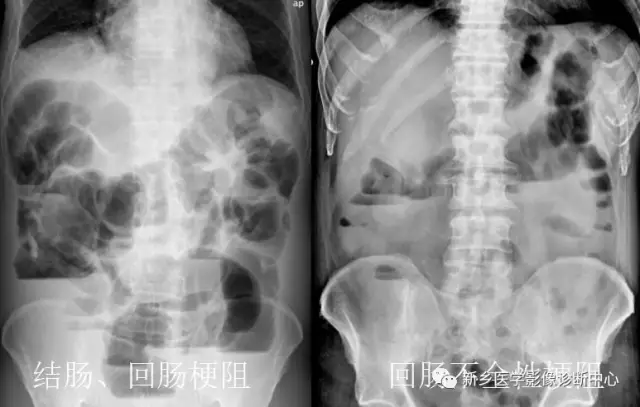

13 肠梗阻

文章图片